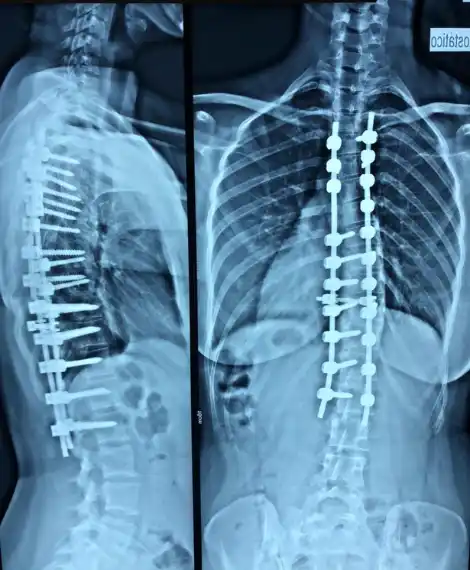

A Cirurgia para Correção de Escoliose

O procedimento cirúrgico para escoliose envolve a instrumentação da coluna com parafusos pediculares e hastes, permitindo a correção tridimensional da deformidade. O planejamento é individualizado, utilizando software 3D para análise da curvatura e definição da estratégia de correção. Durante toda a cirurgia, a monitorização neurológica intraoperatória acompanha a função da medula e raízes nervosas.

O procedimento é realizado sob anestesia geral com monitorização neurológica intraoperatória contínua. Através de acesso posterior, parafusos pediculares são posicionados nos níveis definidos no planejamento. Hastes são moldadas conforme o alinhamento desejado e a correção é realizada progressivamente. A fusão vertebral garante a estabilidade a longo prazo.